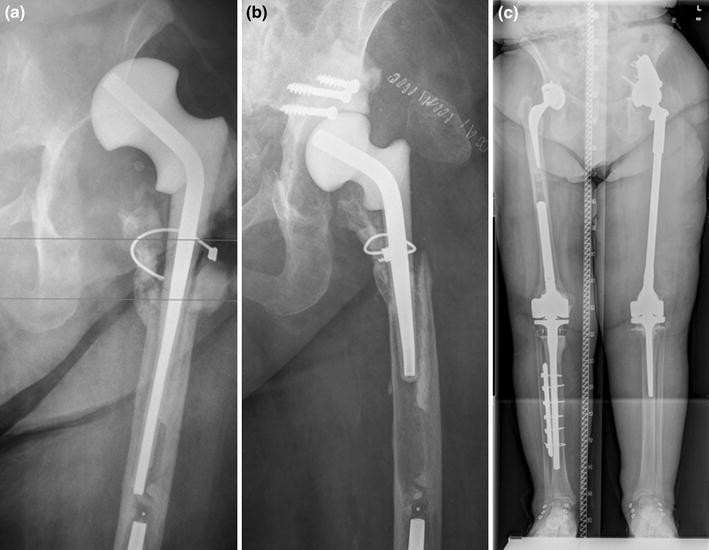

From www.cureus.com

Cureus Mechanical Complications of Hip and Knee Spacers Are Common What Is A Temporary Hip Spacer Interspace offers more than just speed and time. Infected periprosthetic femoral fractures are among the most complex and significant. Its purpose is to maintain the. — i have undergone 5 hip replacements and a few antibiotic hip spacers all on my left hip. there are several different types of spacer: the rehabilitation program following hip spacer implantation. What Is A Temporary Hip Spacer.

From www.researchgate.net

Anteroposterior radiographs of the hip spacer A) without cementation What Is A Temporary Hip Spacer This spacer is treated with antibiotics to. in the first surgery, your doctor will remove the implants and place a temporary cement spacer in your hip. there are several different types of spacer: the rehabilitation program following hip spacer implantation emphasizes early, controlled functional range of motion to. — i have undergone 5 hip replacements and. What Is A Temporary Hip Spacer.